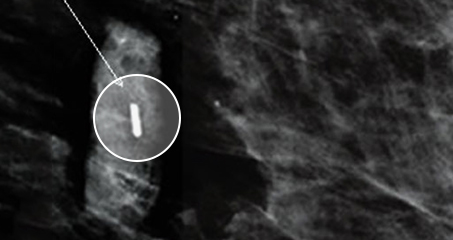

MammoMARK® and CorMARK®

조직을 채취한 위치를 표시하기 위한 체내 표시기

Breast Excision / biopsy

Marker